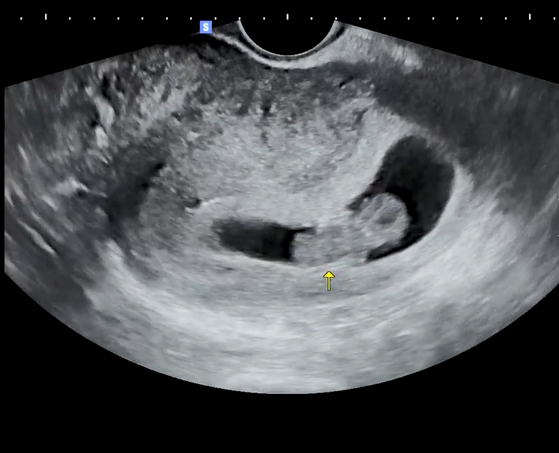

첫째고 임신시도는 3~4년은 한 거 같아요.

올해 초 이젠 너무 갖고 싶어서 병원 열심히 다녔고 드디어 결실을 맺었네요.

첫애가 생기면 꼭 하고 싶었던 여러가지가 있는데 그 중 하나가 펨코에서 축하받는거였네요 ㅎㅎ

다들 축하해주세요